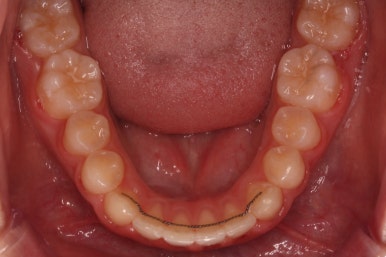

악궁확장장치는 유지기간 이 후 다 제거가 되었고, 치아들이 매우 가지런해지는 것을 볼 수 있습니다.

이제 조금만 더 정리가 되면 장치 제거가 가능하겠네요.

키다리아저씨치과에서 부산비발치교정 전후 사진 비교입니다.

치료 종료 시점에는 위아래 앞니 모두 안쪽에 유지장치를 붙이고 있는 것을 볼 수 있습니다.